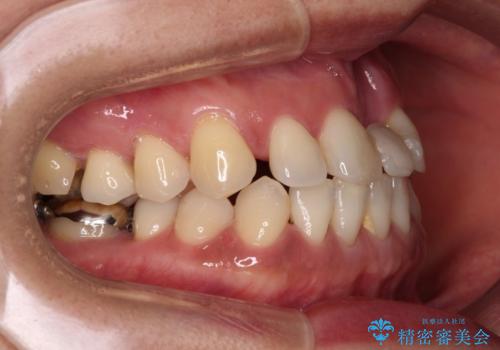

- 矯正治療を行ったものの、隙間やデコボコが多く、欠損している前歯も気になるとのことで来院された患者様です。

当初はセラミック治療だけを希望されていましたが、上下前歯のデコボコが顕著であったため、セラミッククラウンにて治療する前に再度矯正治療を行った方が仕上がりがきれいになると説明し、再矯正を行うこととしました。